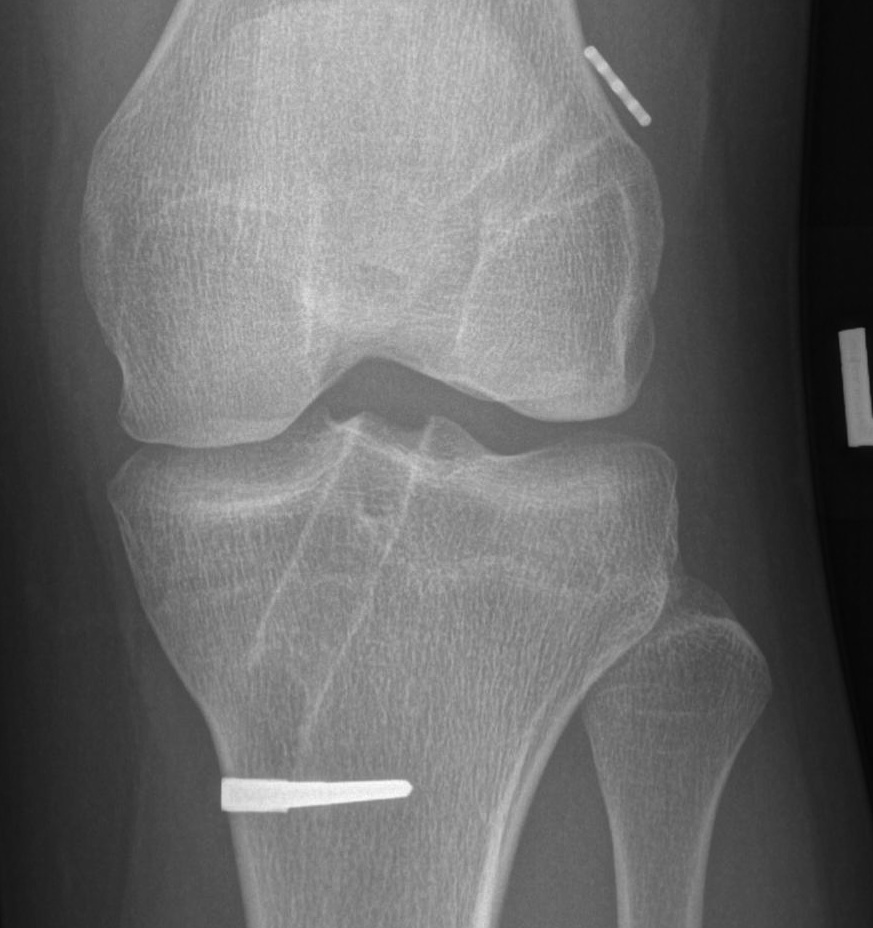

Femoral Tunnel

Most common error in ACL Reconstruction

- errors in femoral placement are less forgiving

- either get a loss of motion or graft failure

Optimal placement

- lateral radiograph

- intersection of Blumensaat's line and

- line extended from the posterior femoral cortex

A. Anterior femoral placement

- increases tension in flexion / loss of flexion

- stretching of the graft required to obtain flexion

B. Posterior femoral placement

- increases tension in extension

- need to stretch to obtain extension

C. Superior femoral placement

- 12 o'clock position

- AP stability

- rotationally unstable / continue to pivot shift